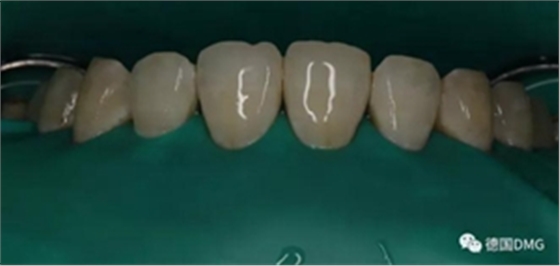

2,使用紅標45μm微米和黃標25μm粒度車針仔細緩慢打磨去除釉質表面高氟鈣化的斑塊和釉質凹坑0.05-0.1mm后,車針打磨后要再使用低速慢機用矽粒子拋光去除釉質表面浮釉(松風矽粒子、樹脂拋光輪),下圖是微打磨后。

(下圖是上頜打磨后與下頜術前未研磨對比,區(qū)分打磨效果和目的)

3,icon鹽酸處理兩分鐘,暴露釉質表面孔隙,表面礦化層厚度減少更明顯,更適合做滲透前釉質處理,獲得更好的滲透深度。(一定要使用橡皮障)

酸蝕后沖洗干凈,吹干表面多余水分